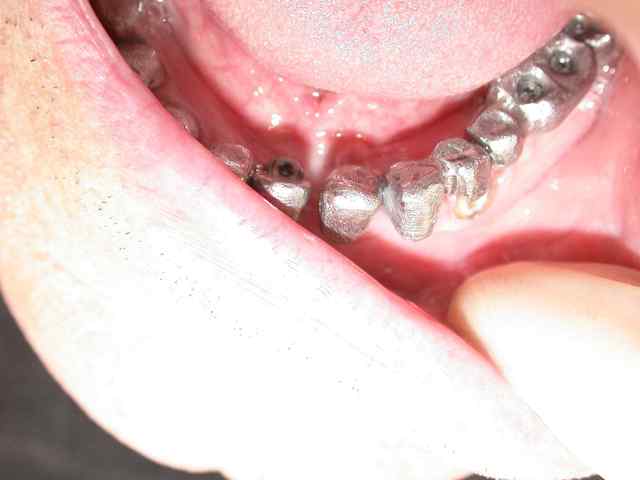

couronnes unitaires sur 42 41 (41 mal située position un peu trop lingual : la vue linguale de la photo montre notre solution prothétique pour l'axe)

pano et photos a suivre les photos sont pas tops car vieil apparei et je vous le rappelle (reflex nauseeux,faut pas aller chercher trop loin quand même , mais vous verrez à la fin on met des écarteurs photos si si...)

Euhhh : Pourquoi avoir fait 46-47 en métal ?? Tout le reste est en céramique, vu le travail important, il est pas à 300 près (au pire c'est cadeau... lol)

Pardon, j'avais pas vu que 36 et 37 étaient aussi en métal.